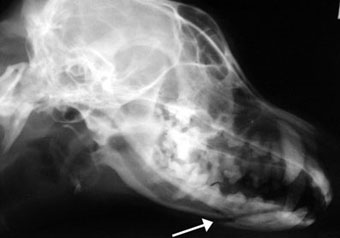

体重6kgの犬の下顎骨折。

創外固定法で整復固定し、4か月半後に抜ピンしました。

写真上段: 手術前

白矢印で示した黒い線が骨折部です。